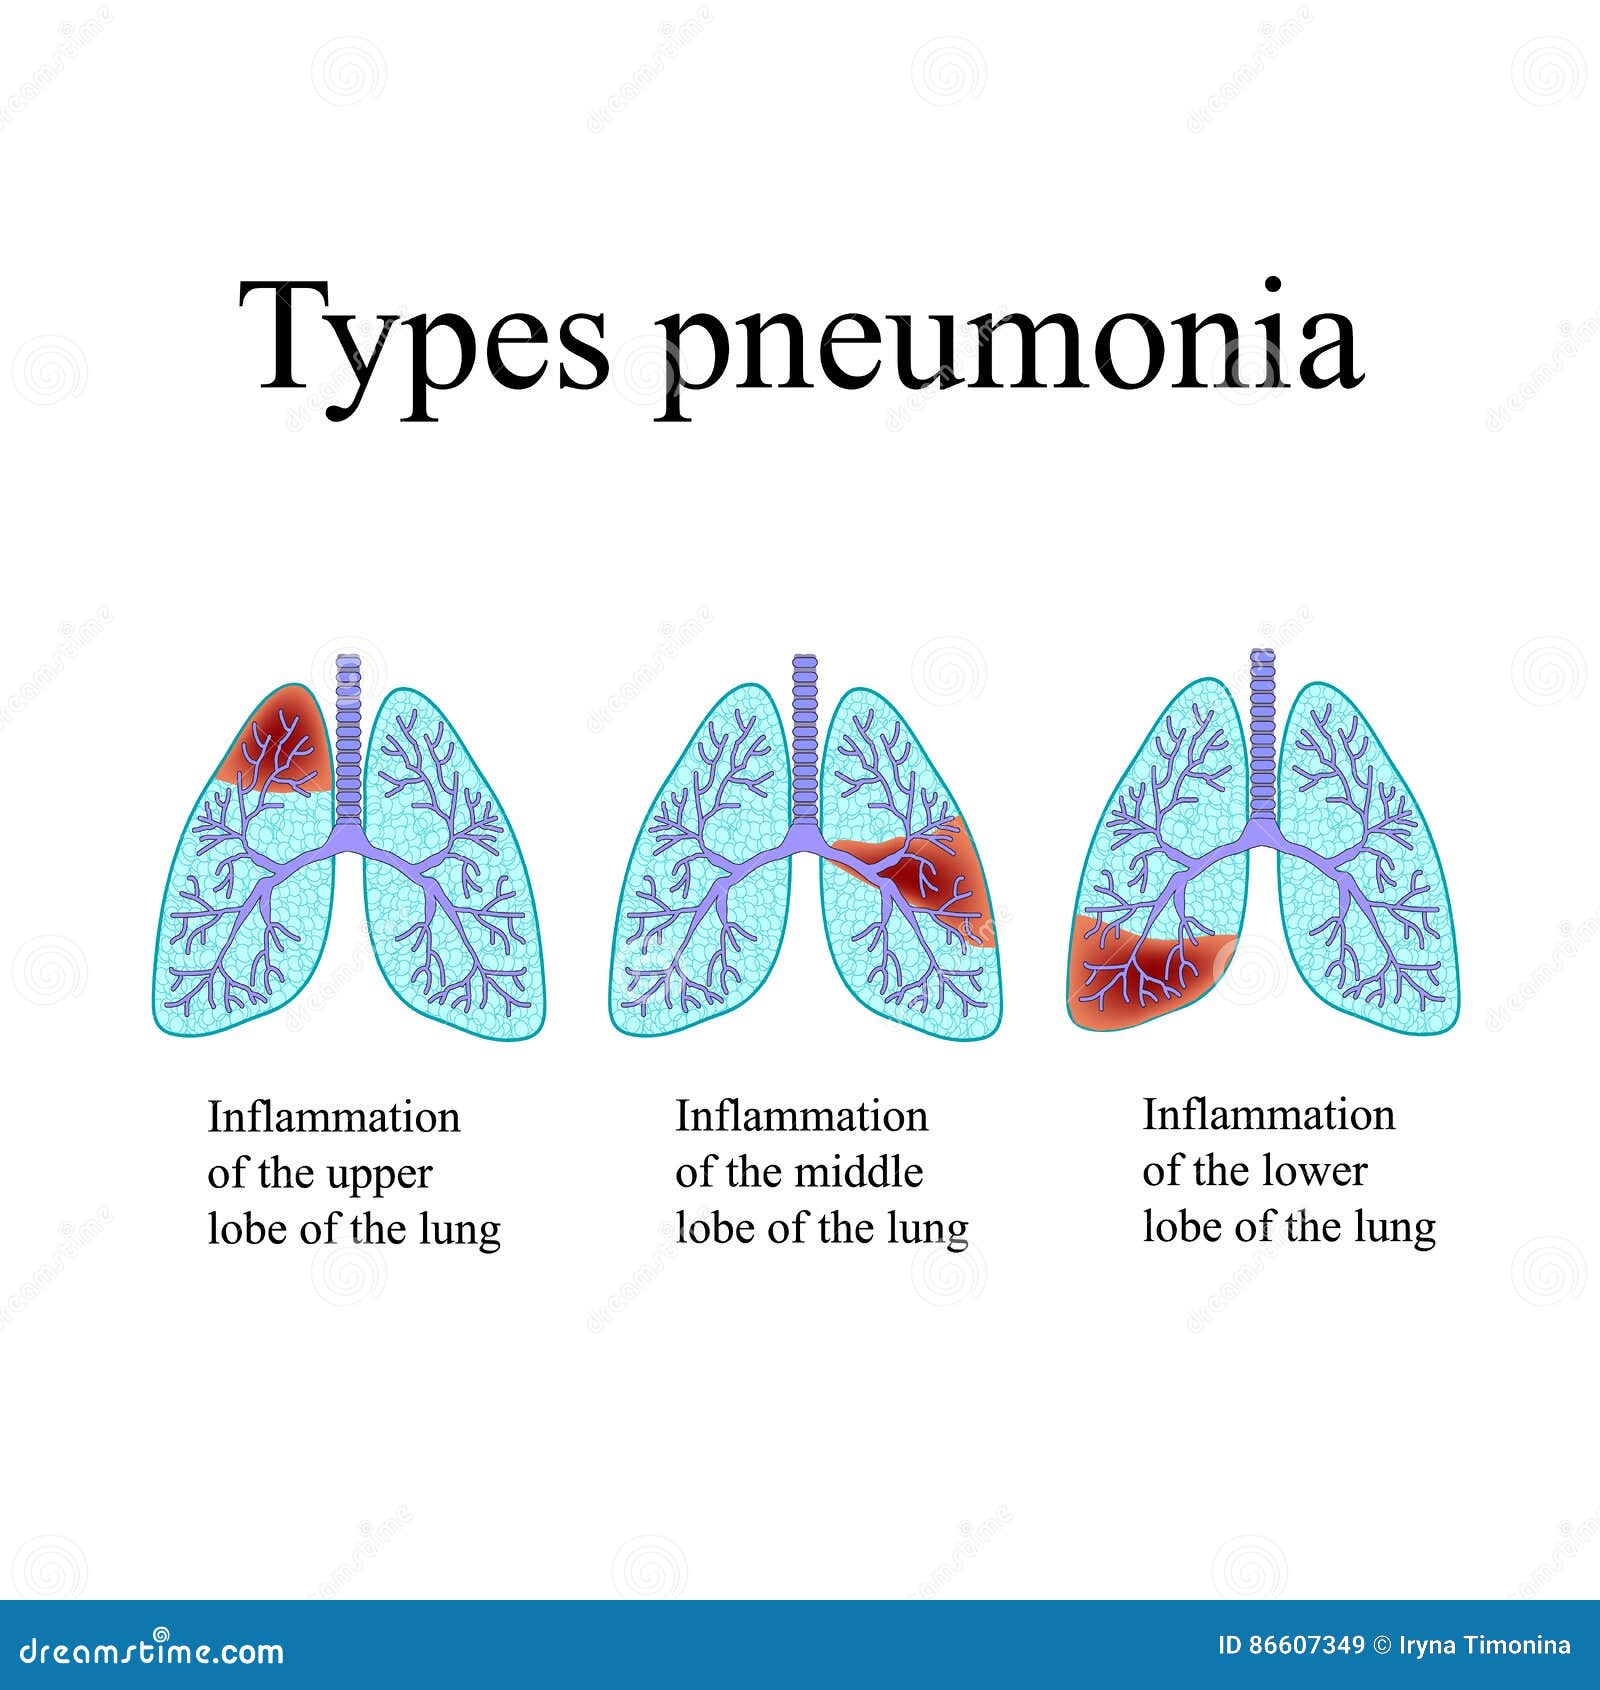

Пневмония - это серьезное заболевание легких, которое может быть вызвано различными причинами, включая бактериальные, вирусные и грибковые инфекции. Для того чтобы наглядно показать симптомы, диагностику и лечение этого заболевания, картинки могут быть очень полезны.

Картинки с симптомами пневмонии

В этом разделе представлены изображения, демонстрирующие различные симптомы пневмонии, такие как кашель, одышка, боль в груди и повышенная температура. Эти картинки могут быть использованы для обучения и презентаций в области медицины и здравоохранения.